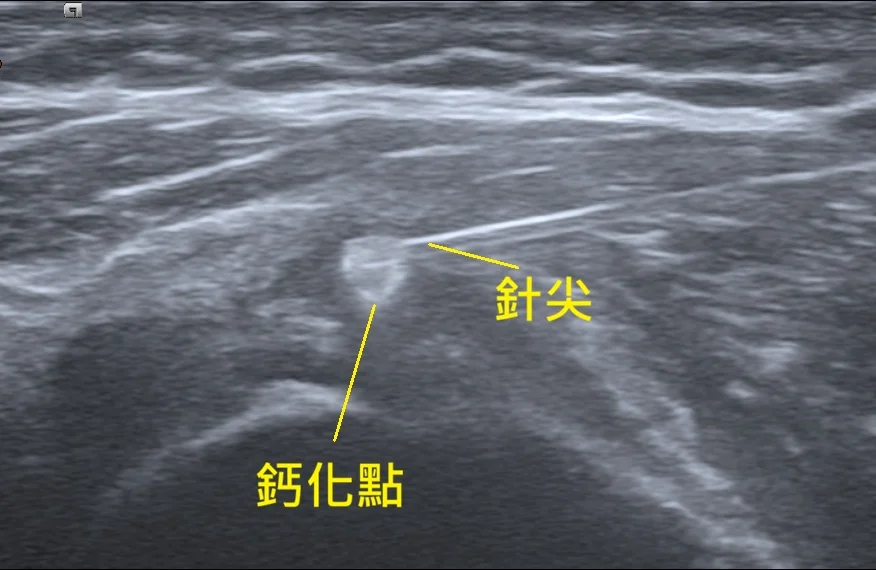

這項技術叫做「超音波導引鈣化沖洗術」 (Barbotage)。我們在即時超音波的監控下,將針頭精準地引導至鈣化中心,利用生理食鹽水反覆沖洗、抽吸。

治療過程中,螢幕上的畫面就像是挖掘工程。一開始那顆巨大的白色結石,隨著我們不斷地沖洗、抽出粉筆灰般的鈣化物,體積肉眼可見地開始縮小、崩解。患者看著螢幕,驚訝地說:「原來裡面真的有這麼多東西!」